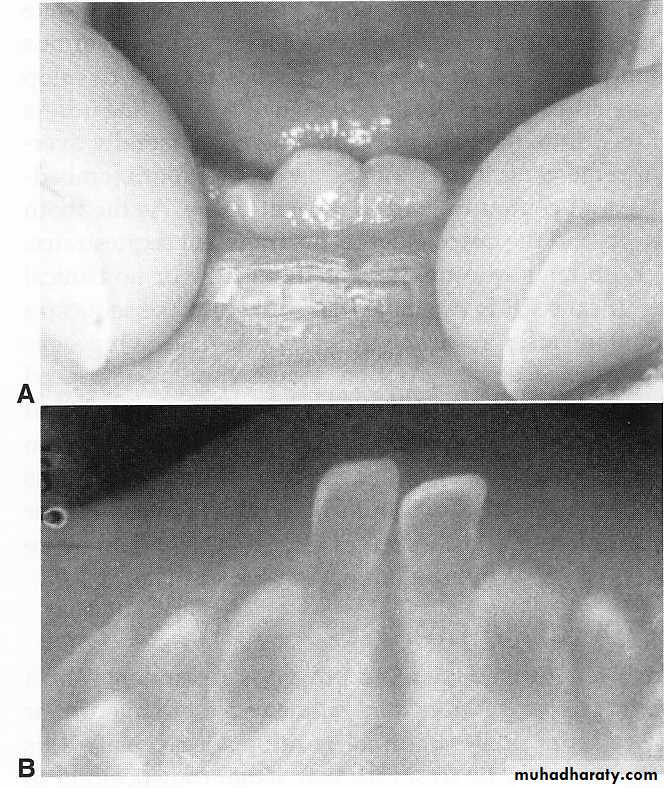

1. ERUPTION HEMATOMA (ERUPTION CYST)

Eruption cystseen occasionally in children at the time of the eruption of the first permanent molar a tiny spicule of nonviable bone overlying the crown of an erupting permanent molar just before or immediately after the emergence of the tips of the cusps through the oral some of these sequestra spontaneously resolve without noticeable symptoms.'

2. ERUPTION SEQUESTRUM

after an eruption sequestrum has surfaced through the mucosa, it may easily be removed if it is causing local irritation.

If the base of the sequestrum is well embedded in gingival tissue when it is discovered,

application of a topical anesthetic or infiltration of a few drops of a local anesthetic may be necessary to avoid discomfort during removal.

ERUPTION SEQUESTRUM